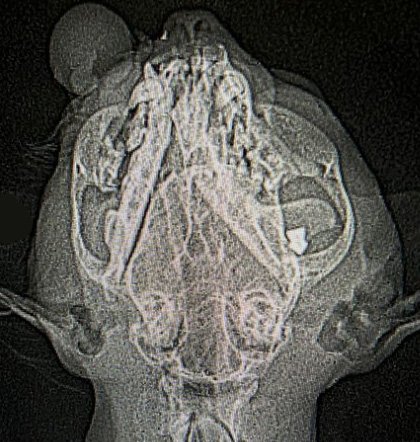

До одного з ужгородських притулків, що опікуються тваринами, потрапив кіт, якому цілеспрямовано вистрелили в око. Про це повідомляють організатори притулку PetCare_UA на своїй сторінці в Instagram.

Ужгород! Ми потребуємо розголосу!!! В мій притулок поступає четверта постріляна тварина, останній кіт був стріляний цілеспрямовано в око! Тепер він лежить на операційному столі, тому що було термінове втручання ! Ми не можемо тягнути і чекати!